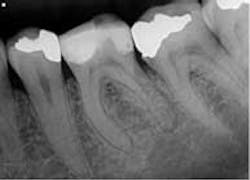

Clinical evaluation revealed no intraoral or extraoral swelling and a large composite restoration in tooth No. 19. Endodontic testing revealed severe pain to cold in tooth No. 19; all other tests were within normal limits (WNL). All other teeth in the quadrant tested WNL. The diagnosis was irreversible pulpitis with normal apical tissue. Radiographic exam revealed a large composite restoration and abnormal anatomy suggesting radix entomolaris. Radix entomolaris is a supernumerary root located distolingually in mandibular molars. The supernumerary root can also be found mesiobucally, and this is called radix paramolaris. The prevalence of a supernumerary root in mandibular molars has been found to be between 2.2% (Skidmore) and 21.5% (Yew and Chan). It is important to carefully study our preoperative and working radiographs in order to recognize the presence and location of abnormal anatomy.